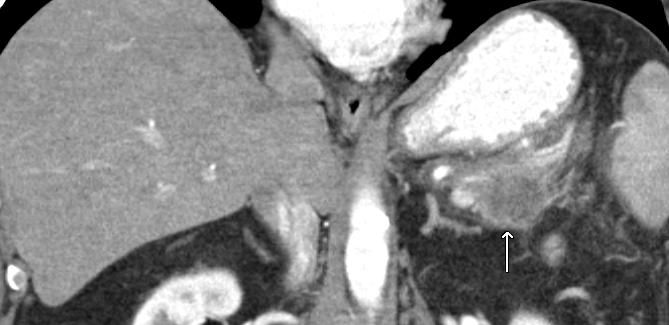

Collision Tumors: Pancreatic Adenocarcinoma and Mantle Cell Lymphoma

Context Collision tumors are very rare entities composed of two or more distinct tumor components, each separated by normal tissue. Perhaps due to technical advances in the last decade, the incidence of collision tumors has been on the rise. To the best of our knowledge, collision tumors featuring mantle cell lymphoma and pancreatic adenocarcinoma have not been previously described in the scientific literature. Case report For the first time, we describe herein the clinical course of a collision tumor between pancreatic adenocarcinoma and mantle cell lymphoma. Discussion We hypothesize several aspects in the pathogenesis of a such event and review the existing literature on collision tumors.

PET/CT scan showing extensive FDG-avid tumor featuring